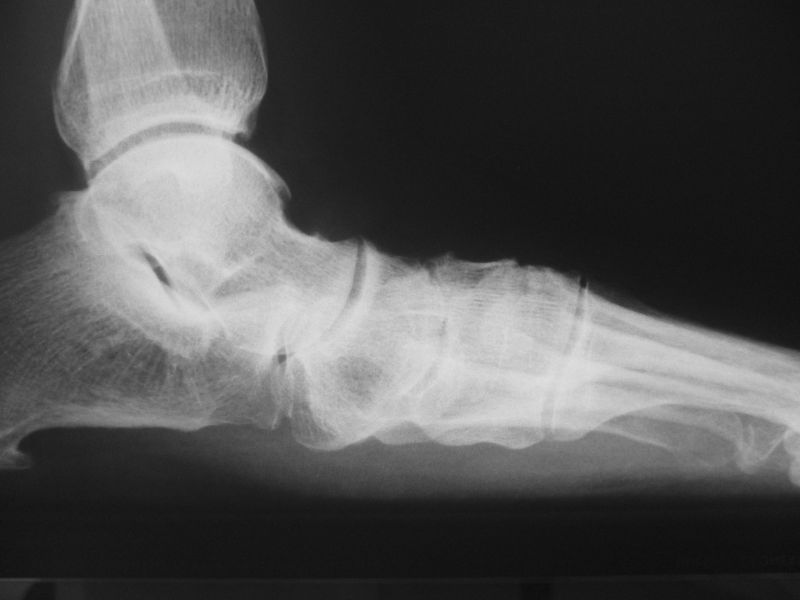

Alte Impressionsfraktur des Os cuboideum mit schweren Knorpelschäden.

Abbildung 9

Die isolierte Arthrose des Calcaneocuboidal-Gelenkes (CC-Gelenk) ist sehr selten. Mögliche Ursachen sind Traumen mit gewaltsamer Abduktion des Mittelfußes gegenüber dem Rückfuß. Der hierfür typische Unfallmechanismus wird meistens bei Zweiradfahrern vorgefunden 33. Impressionen der Gelenkfläche, Ausrisse des Processus anterior calcanei (Insertion des Ligamentum bifurcatum), sowie eine posttraumatische Instabilität des Gelenks können zu degenerative Veränderungen führen.